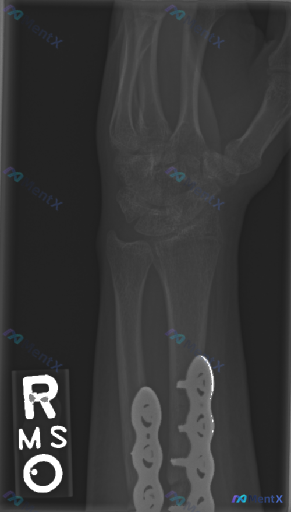

整理到一个右腕关节术后的影像病例,大家一起讨论下。 基本情况 - 背景:右腕关节桡骨远端及尺骨远端骨折术后复查 - 本次检查:右腕关节侧位X光片 影像所见(整理自描述) 1. 骨骼与内固定:桡骨远端及尺骨远端可见金属钢板及螺钉内固定装置;骨折部位皮质对位对线良好,未见新发明显断裂透亮线或台阶感;腕骨...